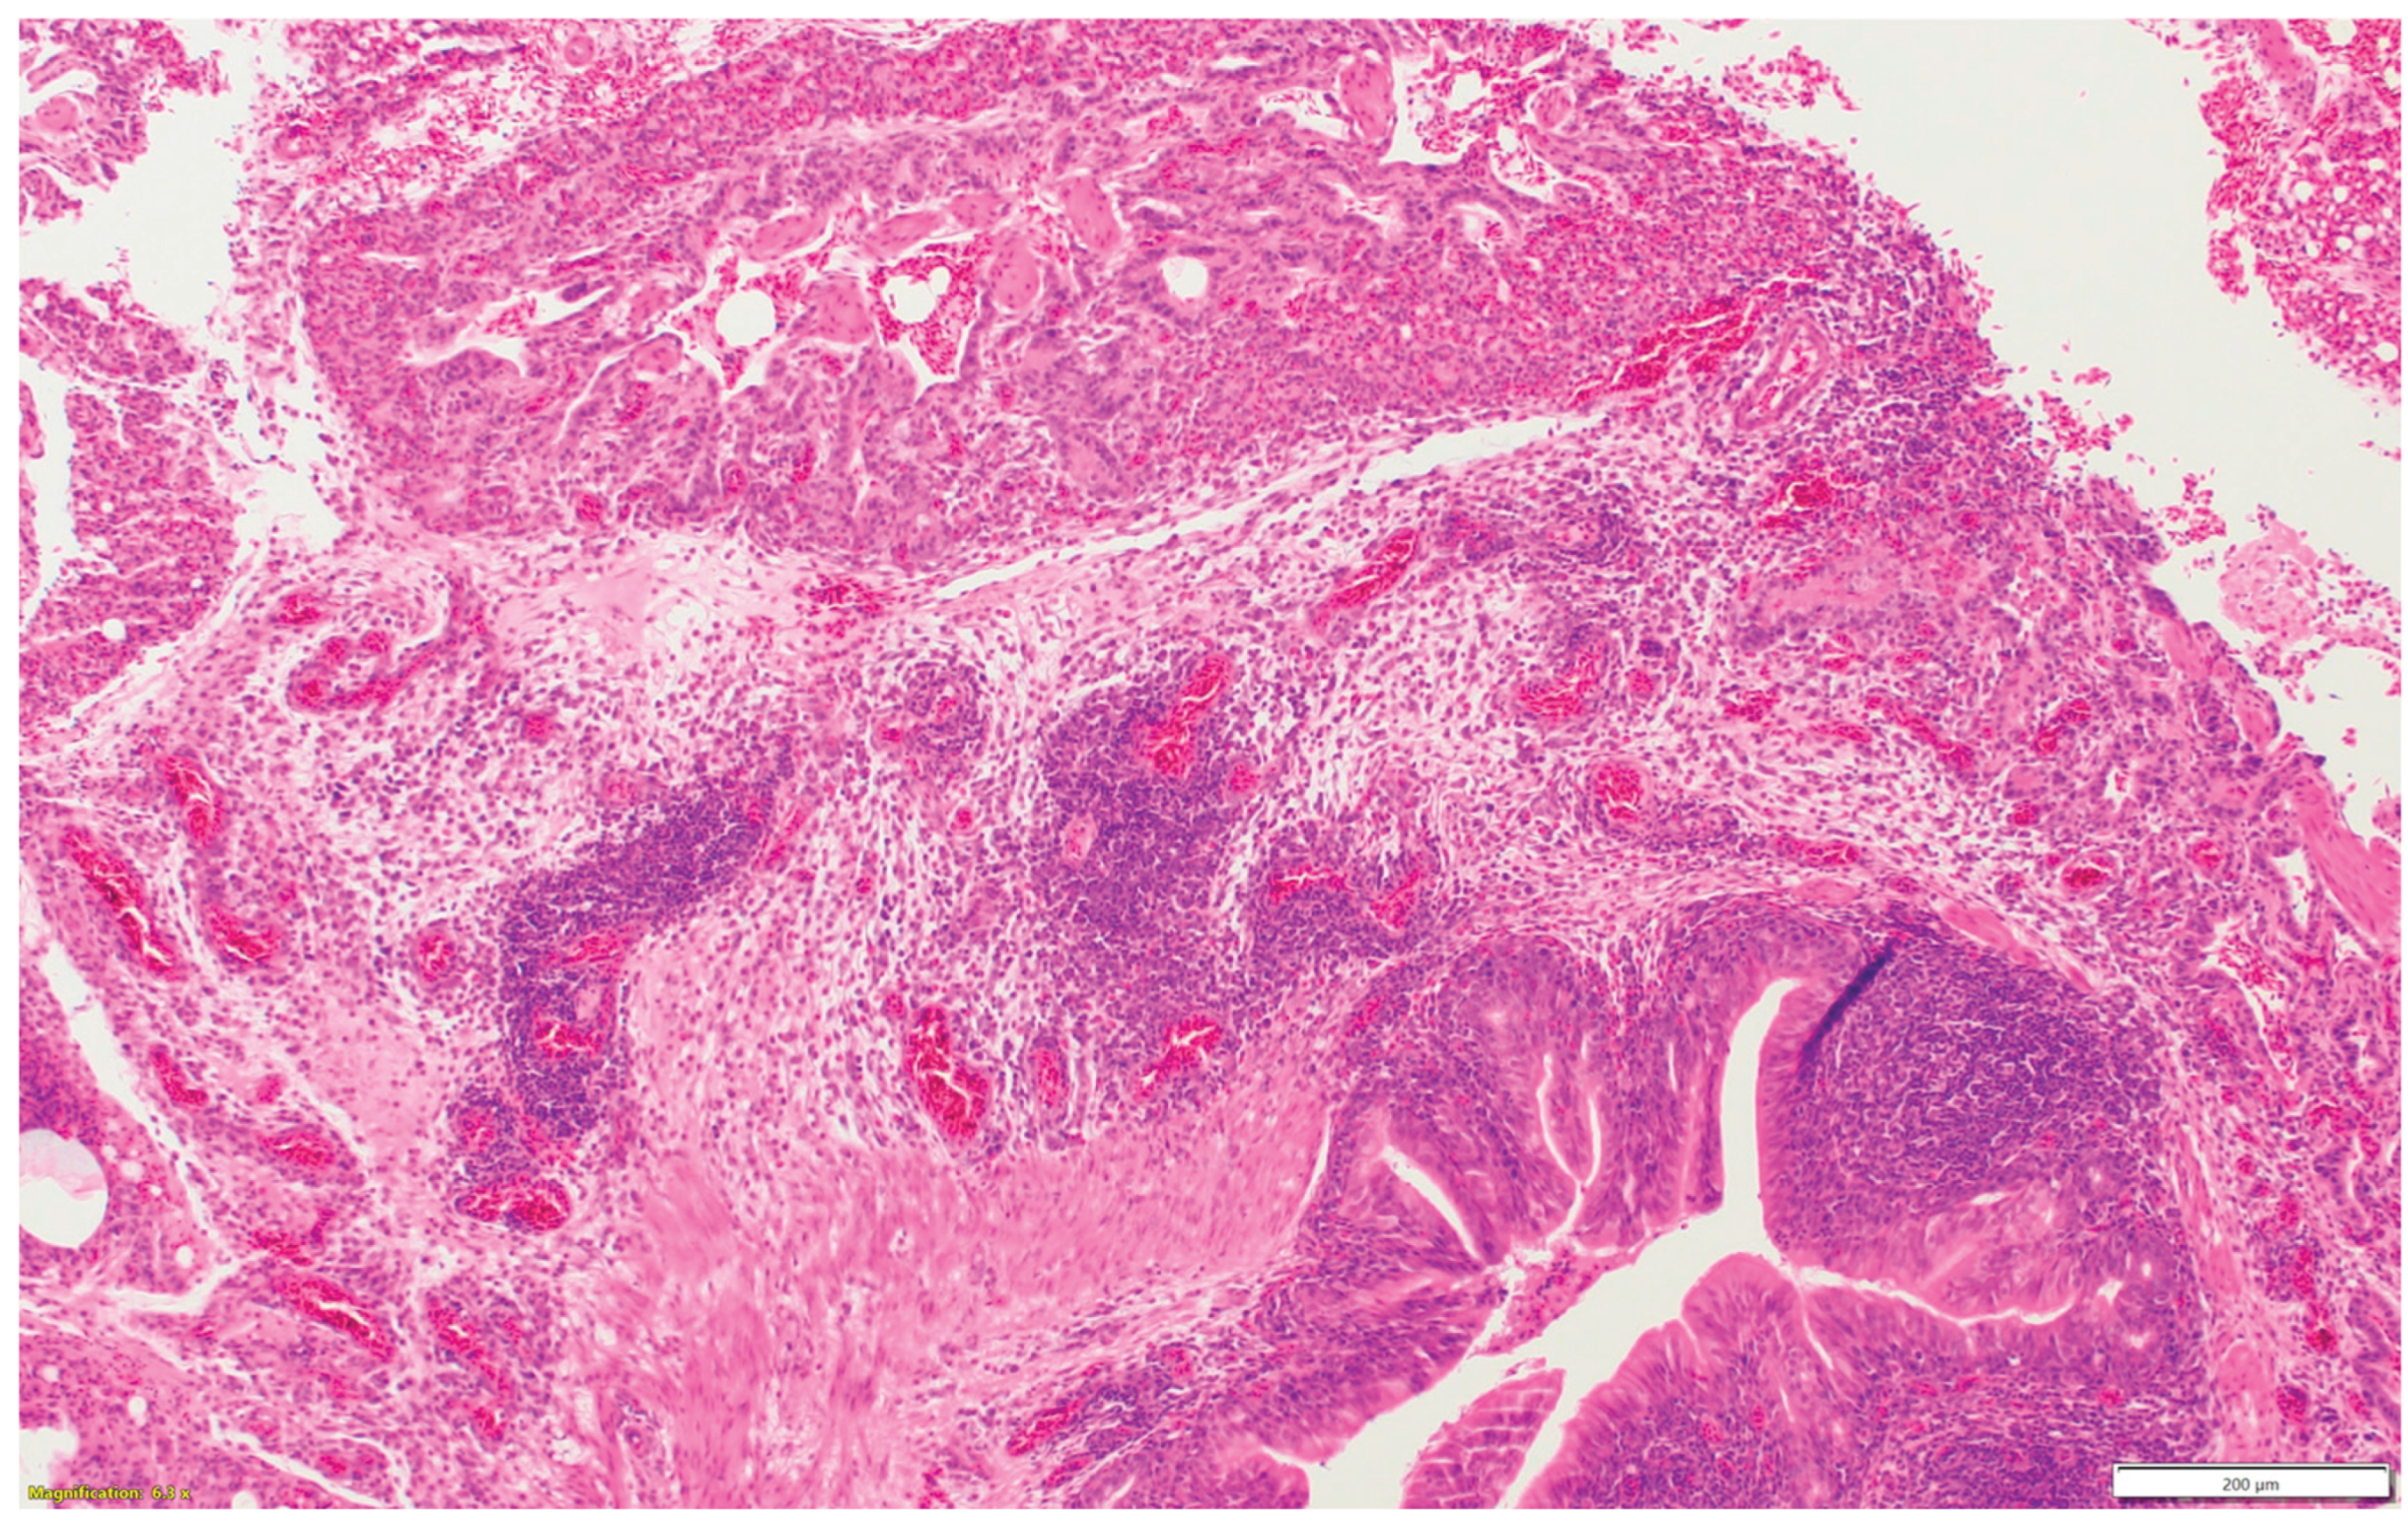

3.3. Turkeys inoculated with aMPV at 7 days of age showed higher lesion scores at 10 DPI compared with the non-infected control group. Sinus and eyelids were the main organs scoring points compared with other organs (Figure 4a).

3.4. Turkeys inoculated with low pathogenic avian influenza (LPAI-H4N6) at 7 days of age had also increased histologic lesion scores at 7 DPI compared with the non-infected control group. Sinus, lungs, eyelids, and trachea were orderly contributing to a higher total HRI (Figure 4b).